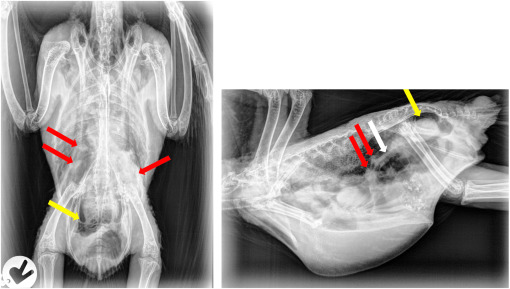

*estudio radiologico. Es una herramienta muy limitada, no siempre se observan las lesiones en las radiografias.